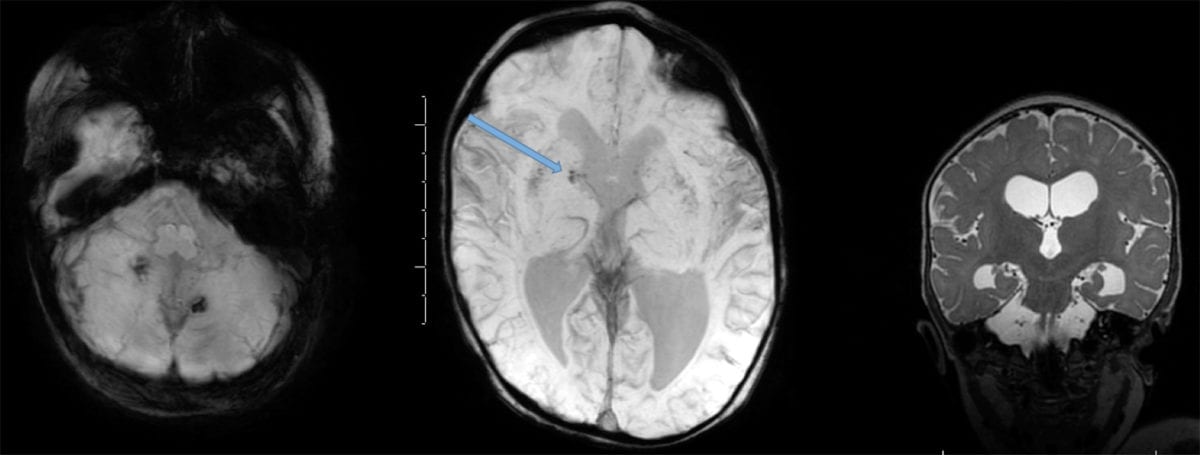

- It is high yield to be able to identify CNS abscess on MRI:

- An abscess will have internal restricted diffusion due to the presence of pus, with a smooth rim of enhancement and adjacent vasogenic edema.

- If multiple lesions are present, consider septic emboli.

- Ventriculitis is another possible complication of meningitis:

- On MRI, ventriculitis appears as fluid levels within the cortical sulci and within the posterior horns of the lateral ventricles with increased signal and on the T1-weighted postcontrast views with extensive enhancement of the ependyma.